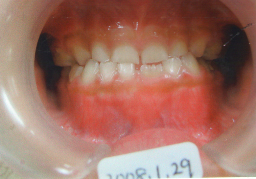

2008年01月29日(6才0ヶ月) 31番(左下切歯)の永久歯がはえてきました。 少し反対咬合 |